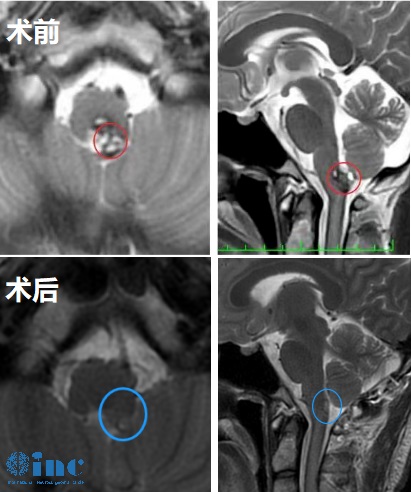

患者情况:35岁的晓玲手术因头晕、恶心呕吐、走路重心不稳、舌体面部麻木等就诊,考虑脑干-桥脑海绵状血管瘤合并静脉畸形,医生告知海绵状血管瘤位置疑难,手术风险很大。虽然症状暂时缓解了,晓玲和家人都知道,寻求手术的机会才能够解决根本问题。多方查询后家人在网上了解到国际脑肿瘤教授INC德国巴特朗菲教授即将在11月份来华进行疑难示范手术,于是争取到了巴教授示范手术的宝贵机会。

治疗过程:2022年11月24日苏州独墅湖医院,巴教授全程主刀手术,在国内神外手术团队的密切配合下,晓玲的脑干桥脑海绵状血管瘤顺利全切,无新发功能损伤。

术后情况:术后3天巴教授查房,晓玲状态良好、对答如流,教授鼓励晓玲术后多坐起来活动。术后8天教授查房,晓玲活动自如,爱笑的她和教授吐槽术后舌头麻有吃饭不香,教授听完表示会慢慢恢复的。术后十一天,巴教授查房,晓婷之前的舌头麻、手指运动障碍等已经恢复很多,拆除了脑内炸弹的她,期待着崭新的明天。